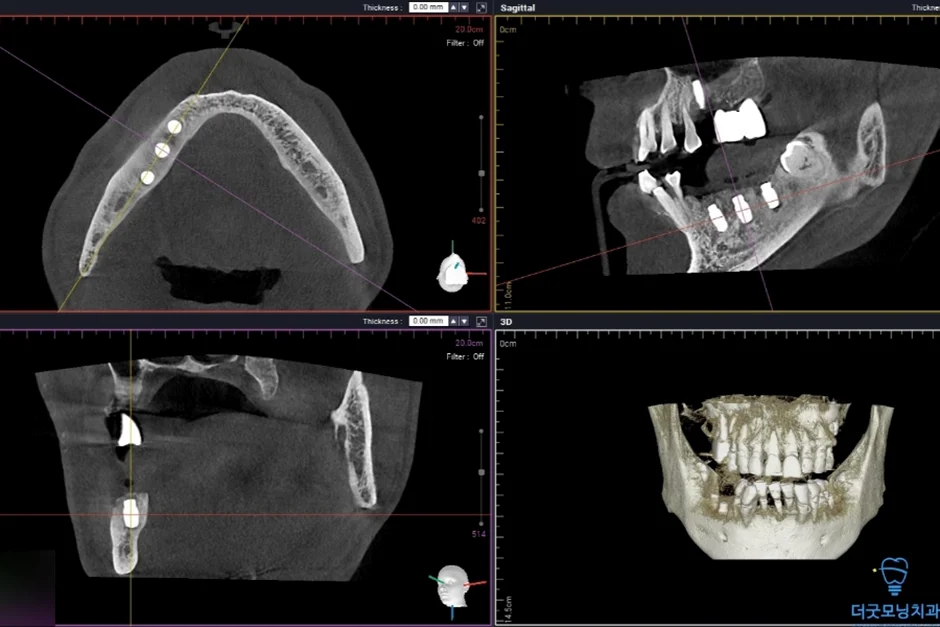

2. 검진 결과 — 파노라마 엑스레이 & CT 분석

먼저 파노라마 엑스레이와 CT를 통해 구강 전체 상태를 확인하였습니다.

■ 아래 양쪽 (하악 좌·우측)

임플란트 주위염이 발생하여 기존 임플란트를 제거하고 재수술이 필요한 상태였습니다. CT 상 신경관까지 어느 정도 거리가 확보되어 재수술은 무리 없이 진행 가능하였습니다.

■ 2차 수술 (왼쪽)

환자분이 충분히 회복하신 이후 반대쪽도 동일하게 수면치료로 진행하였습니다.

노란색 표시처럼 임플란트 식립 잘 마쳤습니다.

두 번째 수술에서도 임플란트가 CT 상에서 확인될 만큼 정확하고 안정적으로 식립되었습니다.